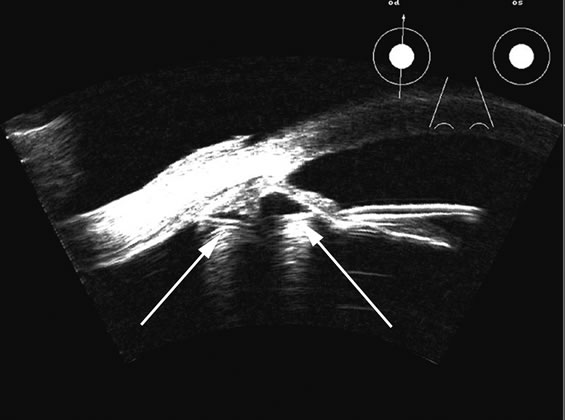

Hypotony is easily diagnosed by direct measurement of intraocular pressure, but the underlying cause is difficult to evaluate.11 High-frequency ultrasound scans can easily reveal separation of the ciliary body and the sclera. This allows different forms of hypotony to be determined—for example: tractional with membrane attached; primary as idiopathic, often inflammatory or hemorrhagic; and dehiscence secondary to iridodialysis or scleral perforation (Fig. 6).

Fig. 6. Hypotony of the eye generally is easily diagnosed by a separation of the ciliary body from the sclera. We have noted several types of such separation, such as tractional, primary (idiopathic), and dehiscence secondary to iridodialysis or scleral perforation, as in filtration procedures. In our series, greater than two clock hours of separation is typical of hypotony. The lower figure shows a concomitant thickening of the retina-choroid complex, also seen in hypotony (arrows). Long-standing hypotony typically has a shortened globe and possible retinal or choroidal separation.